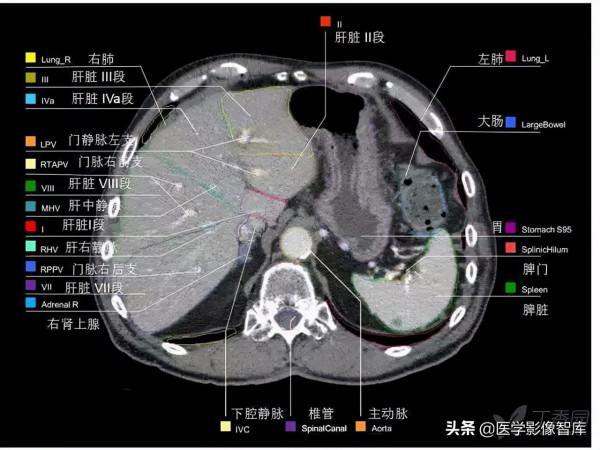

第十四層:肝靜脈水平

1. Intercostal muscle 肋間肌

2. Rib 肋骨

3. External oblique muscle 腹外肌

4. Right hepatic vein 肝右靜脈

5. Inferior vena cava 下腔靜脈

6. Left hepatic vein 肝左靜脈

7. Diaphragm 膈肌

8. Vagus nerve 迷走神經

9. Esophagus 食管

10. Liver (left lobe) 肝左葉

11. Rectus abdominis muscle 腹直肌

12. Stomach 胃

13. Left lung 左肺

14. Latissimus dorsi muscle 背闊肌

15. Liver (right lobe) 肝右葉

16. Right lung 右肺

17. Sympathetic trunk 交感幹

18. Erector spinae muscle 豎脊肌

19. Azygos vein 奇靜脈

20. Thoracic duct 胸導管

21. Spinal cord 脊髓

22. Thoracic vertebra 胸椎

23. Descending aorta 降主動脈

24. Posterior vagal trunk 迷走神經後幹

25. Spleen 脾臟

26. Intercostal lymph nodes

肋間淋巴結

27. Paravertebral lymph nodes

椎旁淋巴結

28. Para-aortal lymph nodes

主動脈旁淋巴結

29. Superior phrenic lymph nodes

膈上淋巴結

30. Inferior phrenic lymph nodes

膈下淋巴結

31. Right gastric lymph nodes

胃右淋巴結

32. Left gastroomental lymph nodes

胃網膜左淋巴結

Right Lung 右肺

9. Lateral basal segment of lower lobe

下葉外側基底段

10. Posterior basal segment of lower lobe

下葉後基底段

Left Lung 左肺

5. Inferior lingular segment

下舌段

8. Anterior basal segment of lower lobe

下葉前基底段